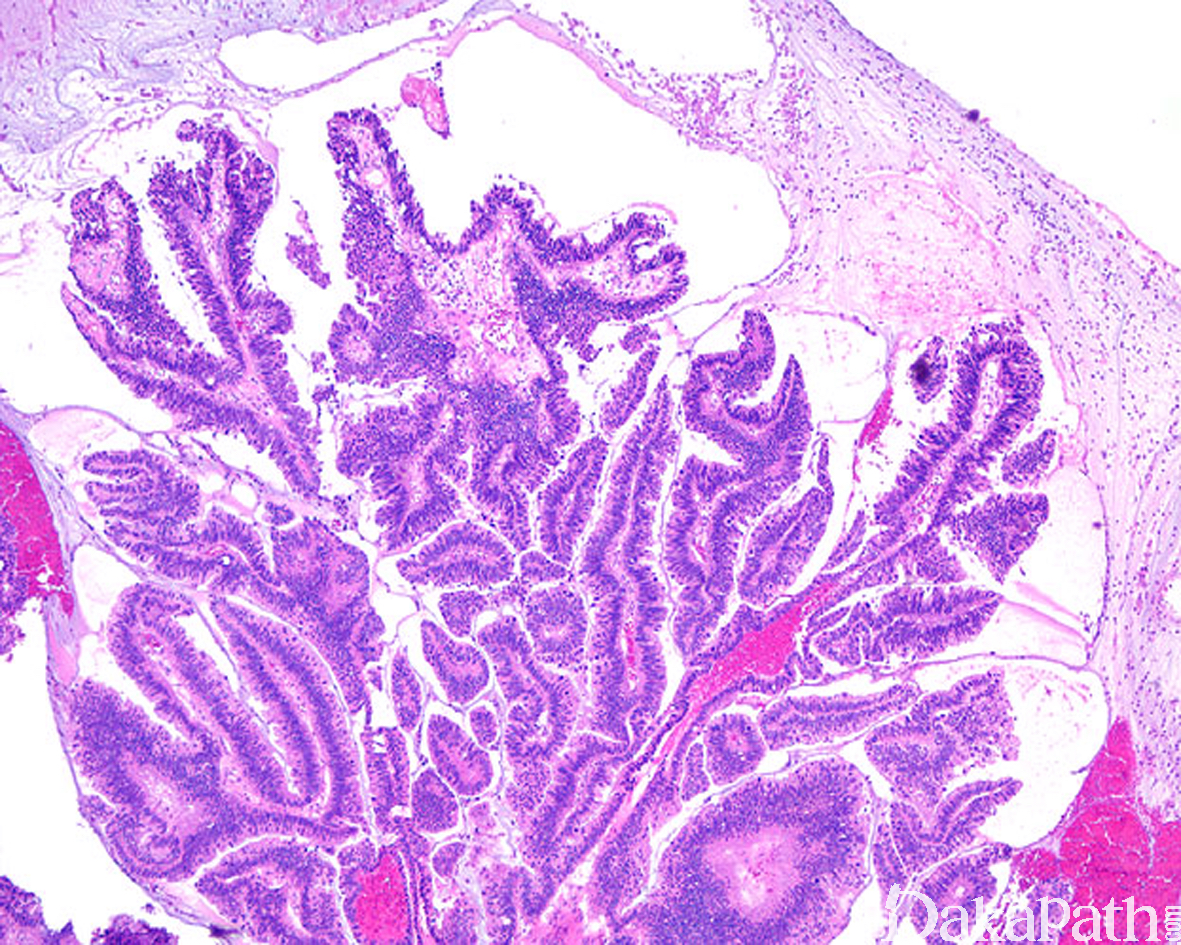

- 膀胱镜检多表现为外生性乳头状肿瘤,与乳头状尿路上皮癌在大体上无法区分;

- 镜下呈具有纤维血管轴心的乳头状结构,或尖锐或钝性指状突起,被覆肠型上皮;有时可表现为管状腺瘤或管状绒毛状腺瘤;

- 上皮具不同程度的异型性,多数呈低级别上皮内瘤变,也可见高级别上皮内瘤变甚至原位癌;约 35%伴随有浸润性腺癌;